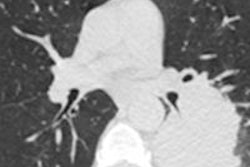

CT image shows primary lung invasive mucinous adenocarcinoma in right upper lobe presenting as air-space consolidation with air bronchograms in 68-year-old man. Ill-defined centrilobular nodules (arrows) with ground-glass attenuation are present posterior to lesion."Growing evidence in the literature suggests that aerogenous spread of lung adenocarcinoma is an underrecognized form of tumor progression, having distinct pathologic and imaging findings and potentially major management implications," the authors concluded. "The presence of persistent or growing centrilobular nodules on CT images should be considered suspicious for aerogenous spread in patients with primary lung adenocarcinoma, particularly those with invasive mucinous, papillary, and micropapillary subtypes."